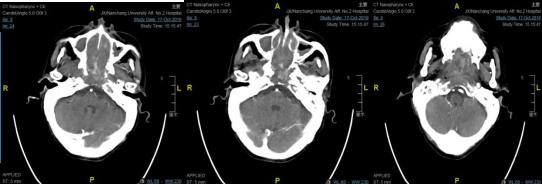

该患者是一位70岁男性,21年前患者因"鼻咽恶性肿瘤"曾行放疗,于5月余前出现鼻腔反复出血,伴鼻塞、说话含糊不清,反复至国内多家三甲医院就诊,因患者年事已高、体质差,均未能给予进一步治疗。因反复出血,致使老人每日生活在恐惧之中,期盼着能得到救治。进入南大二附院耳鼻咽喉头颈外科治疗时,患者已合并极重度贫血、低钠低氯血症、低蛋白血症,并且仍有反复出血、纳差,入院诊断:鼻咽恶性肿瘤,失血性贫血,低钠低氯血症,低蛋白血症。该科鼻-鼻颅底团队经过反复讨论,针对患者病情危重、肿瘤巨大、体质差易导致手术风险和难度极大的情况,鼻-鼻颅底团队认真制定手术方案,决定先行介入下颈外动脉栓塞,再在全麻下行鼻内镜下鼻咽颅底肿瘤扩大切除术。

10月21日,南大二附院综合介入室陈平主任带领的介入团队于局麻下行血管介入下颈外动脉栓塞,完成介入手术后立即送至手术室,由盛洪广主任带领的麻醉团队成功完成全身麻醉,由耳鼻咽喉头颈外科鼻-鼻颅底团队在全身麻醉下行鼻内镜下鼻咽颅底肿瘤扩大切除术,术中顺利切除鼻咽部巨大肿瘤,并将侵犯蝶窦、斜坡、左侧破裂孔区肿瘤完整切除,术中出血不多,手术全程仅用时2小时。

手术前